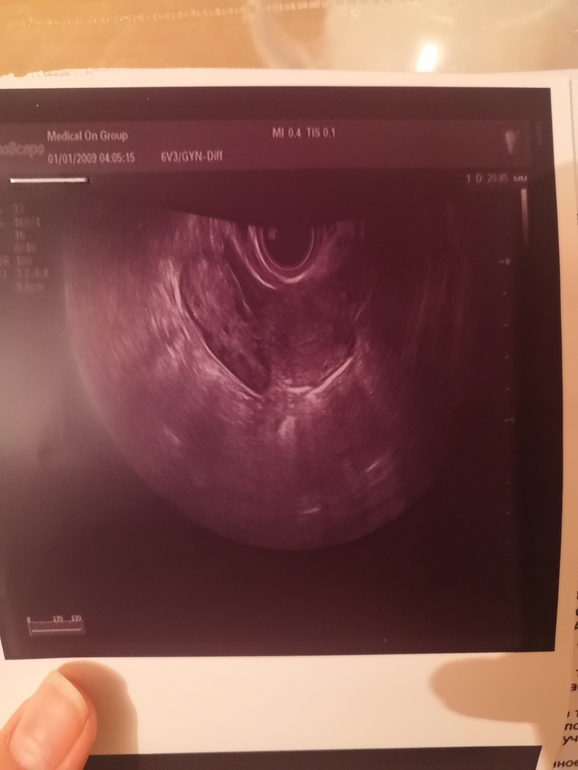

Всем привет 😊 на Узи сказали вроде овуляция была, сделала тест на овуляцию. Все таки была или нет?